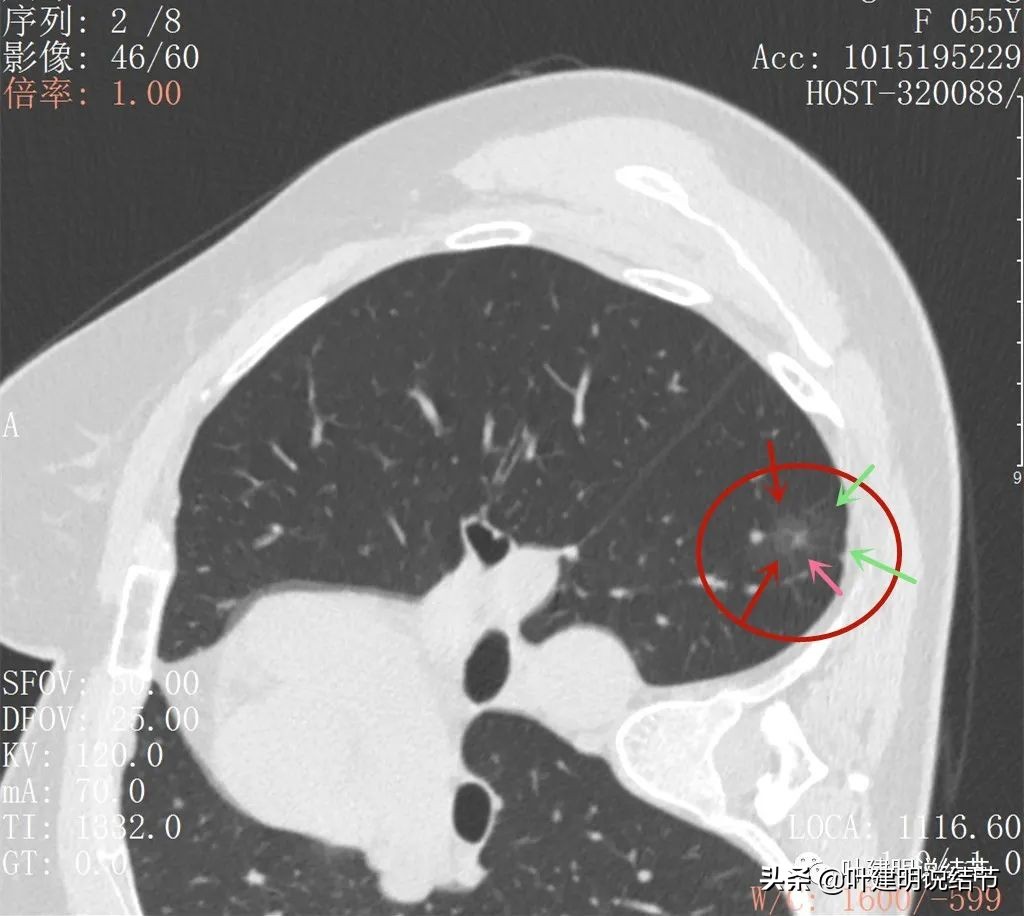

大病灶出现,密度甚淡,有血管进入的样子(桔色箭头),磨玻璃成分明显(绿色箭头),整体看,轮廓还是比较清楚的(红色箭头)

边略显模糊,主要是密度低,中间有小范围密度偏高(粉色箭头)

磨玻璃部分的密度非常淡,但轮廓相对来说还是看得清

灶内有血管穿行,表现为条状高密度,且不平整(粉色箭头),磨玻璃部分密度很淡